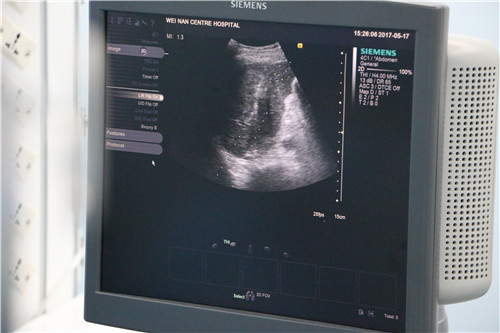

为获得更清楚的影像,功能科将高端台式彩色多普勒超声诊断仪放置在手术间,由超声科丁鹏主治医师负责超声引导,肿瘤外科二病区姜永红副主任负责微波消融针的穿刺操作,郑百鹤护士配合手术。在超声显示屏上,可以清晰地看到肿瘤的位置和范围,微波针在体内走向清晰,成功避开正常肝组织及周围的胆管、血管,准确插入肿瘤中心位置,释放微波,通过高温将肿瘤“烧”死。整个消融手术用时仅40分钟,术后超声显示肝内肿瘤已完全灭活,手术获得成功,目前患者恢复良好。